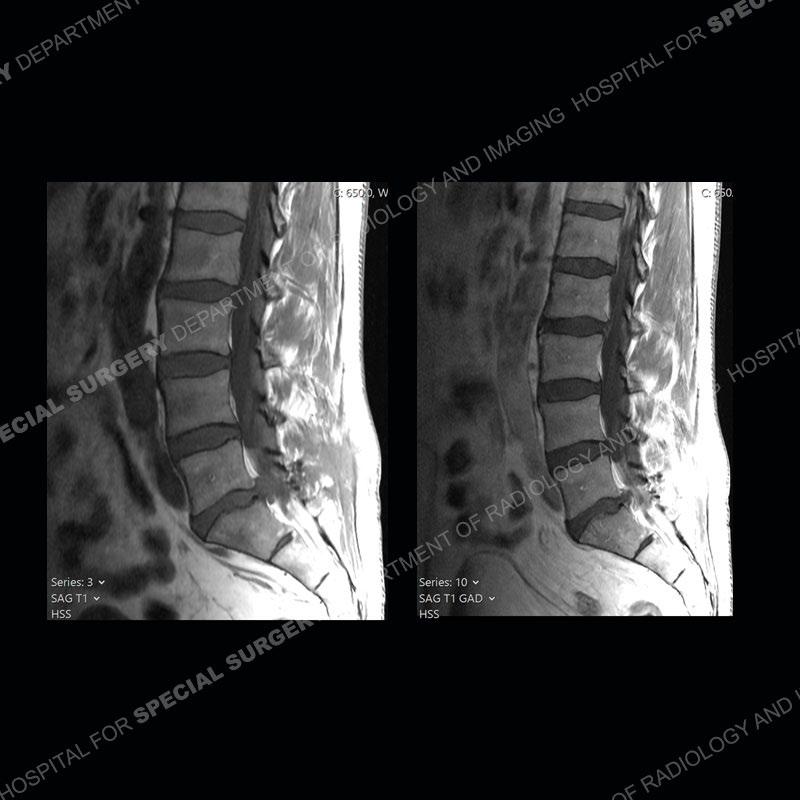

Post operative changes are seen on the left side at L5-S1 where there is near complete removal of the left sided L5 lamina, partial resection of the left L5-S1 facet joint, and resection of the left sided ligamentum flavum. In the anterolateral epidural space about the subarticular recess is a mass that demonstrates similar T1 and T2 signal characteristics to the adjacent degenerated disc. There is enhancement about the periphery of the mass, but the majority of this somewhat geographic or polyploid mass demonstrates no enhancement. The mass exerts prominent mass effect on the left S1 axillary sleeve/proximal nerve root. The left S1 nerve root shows enlargement and increased enhancement as compared to the contralateral right side.

Diagnosis: Recurrent Disc Herniation

Not as much of a diagnostic dilemma as some other cases but more so just a very nice example of what can be a difficult assessment at times. The evaluation of granulation tissue/scar/epidural fibrosis vs. disc herniation particularly in the earlier post operative period can be very difficult. Clues that can assist in identifying a disc herniation are a more geographic or polypoid nature to the mass, signal characteristics similar to the adjacent degenerated disc, mass effect upon the thecal sac/adjacent neural structures, and a typical enhancement pattern. As the disc material is avascular, as long as imaging is performed in a relatively rapid fashion after contrast administration (within 20-30 minutes), the granulation tissue around the disc will enhance but the disc material itself will not. If there is a marked delay between contrast administration and imaging, there may be diffusion of contrast into the disc making the assessment very difficult. The marked utility of contrast to help delineate disc vs. scar has led to our institution employing contrast fairly uniformly within the first two years following surgery.